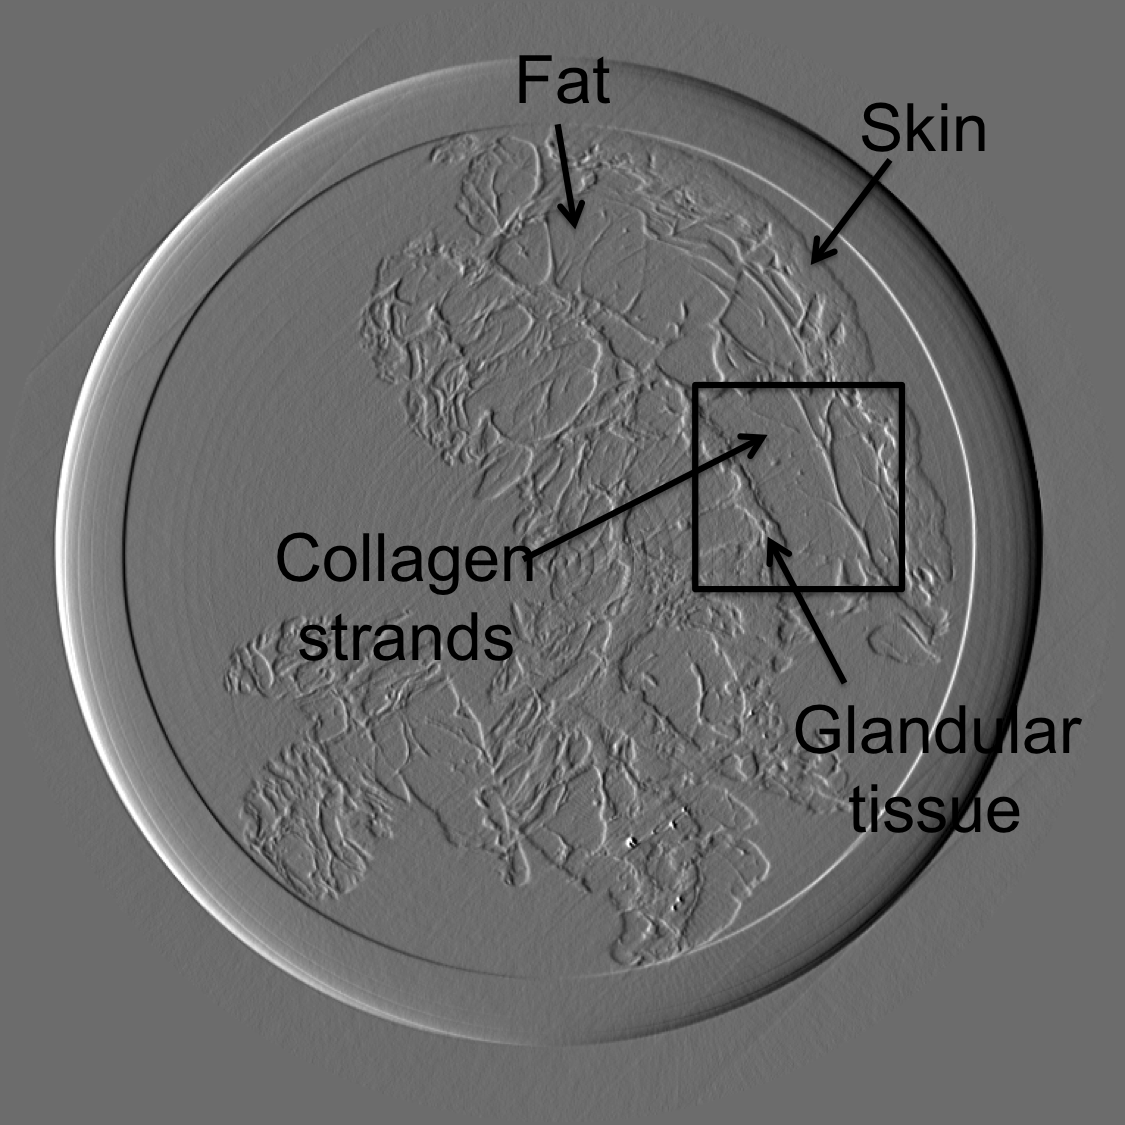

The sample studied is a 7cm human breast imaged with a pixel size of 100 m. The experiment was conducted at the biomedical beam line at the European Synchrotron Radiation Facility (ESRF). The sample was a human breast mastectomy specimen. The study was performed in accordance with the Declaration of Helsinki and was approved by the local ethics committee. A monochromatic X-ray beam with energy of 60 keV was used to image the breast cancer sample. Result of reconstruction is shown in figure 10(top). On this image, radiologists could easily identify the skin, fat and glandular tissue.

Figure 10 is the reconstruction for a pixels slice, using only 200 projections over the 1000 available. The upper left square is a zoom in the region marked in sub figure 10. The right column is the reconstruction with our method for X and Y components, while the left column is reconstructed with standard filtered back-projection using all 1000 available projections. Using our method we can still generate a high quality image with only one fifth of the projections which would be otherwise necessary to generate a high quality reconstruction with the standard FBP method. Visually the difference between the FBP results obtained with full data set and our method with a five-fold reduction of data is barely noticeable. The different borders of structures like skin layers, fatty tissues, and collagen strands are easily identified. The obtained result are very promising and a systematic evaluation for clinical application is under-way. The radiation dose absorbed by the sample during 200 projections is comparable to that of a standard clinical dual view (2D) mammography (3.5mGy).

For an eventual future clinical application of the PCI method it is important to investigate which is the acceptable compromise in terms of low dose and sufficient level of image quality. We need therefore to better explore how the quality of the reconstruction is degraded when we reduce the dose (i.e. number of projections and the acquisition time) further below the standard values. To this end, we performed a reconstruction with only 125 projections and results are shown in the figure III-D for one gradient differential image.

For an eventual future clinical application of the PCI method it is important to investigate which is the acceptable compromise in terms of low dose and sufficient level of image quality. We need therefore to better explore how the quality of the reconstruction is degraded when we reduce the dose (i.e. number of projections and the acquisition time) further below the standard values. To this end, we performed a reconstruction with only 125 projections and results are shown in the figure11. The first column present the result using our method, the second column is the result of reconstruction using FBP algorithm.

If a slightly higher noise level is tolerable, the method may be used with very few projections and thus applied to the screening and diagnosis of human breast cancers with an even lower radiation dose than conventional dual mammography. The results of our reconstruction show an image quality and a capability of discriminating fine structures that are still clinically acceptable. On the contrary, images produced with the standard FBP reconstruction method are very noisy and not diagnostically satisfactory.